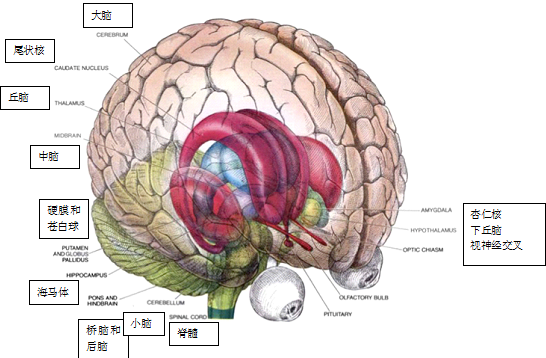

大脑解剖结构的系列雕刻模型,1902年由查尔斯·贝尔爵士制作(伦敦维尔康姆图书馆提供)

如果说过去的图片能够成为未来的向导,这并不全面。传统的大脑解剖学插图(如下图)于1948年首次出现在《美国科学人》上,当时的杂志已经开始刊登医学研究相关信息。

图片来自1948年10月《科学美国人》“巨大而凌乱的结”一文,作者:George W. Gray,插图作者:Eric Mose

数十年过去了,这样的插图依然顽强地存在着。

图片来自1979年9月《科学美国人》“大脑结构”一文,作者:Walle J. H. Nauta 和 Michael Feirtag,插图作者:Carol Donner

尽管PET扫描或MRI这样的成像技术越来越为非专业读者所熟知,并越发频繁地出现在主流媒体中,人们依然没有认为传统的解剖学插图已然过时。也就是说,为了赋予新研究更大的规模和复杂性,我们将需要努力推动具象的插图,使其更好地发展。